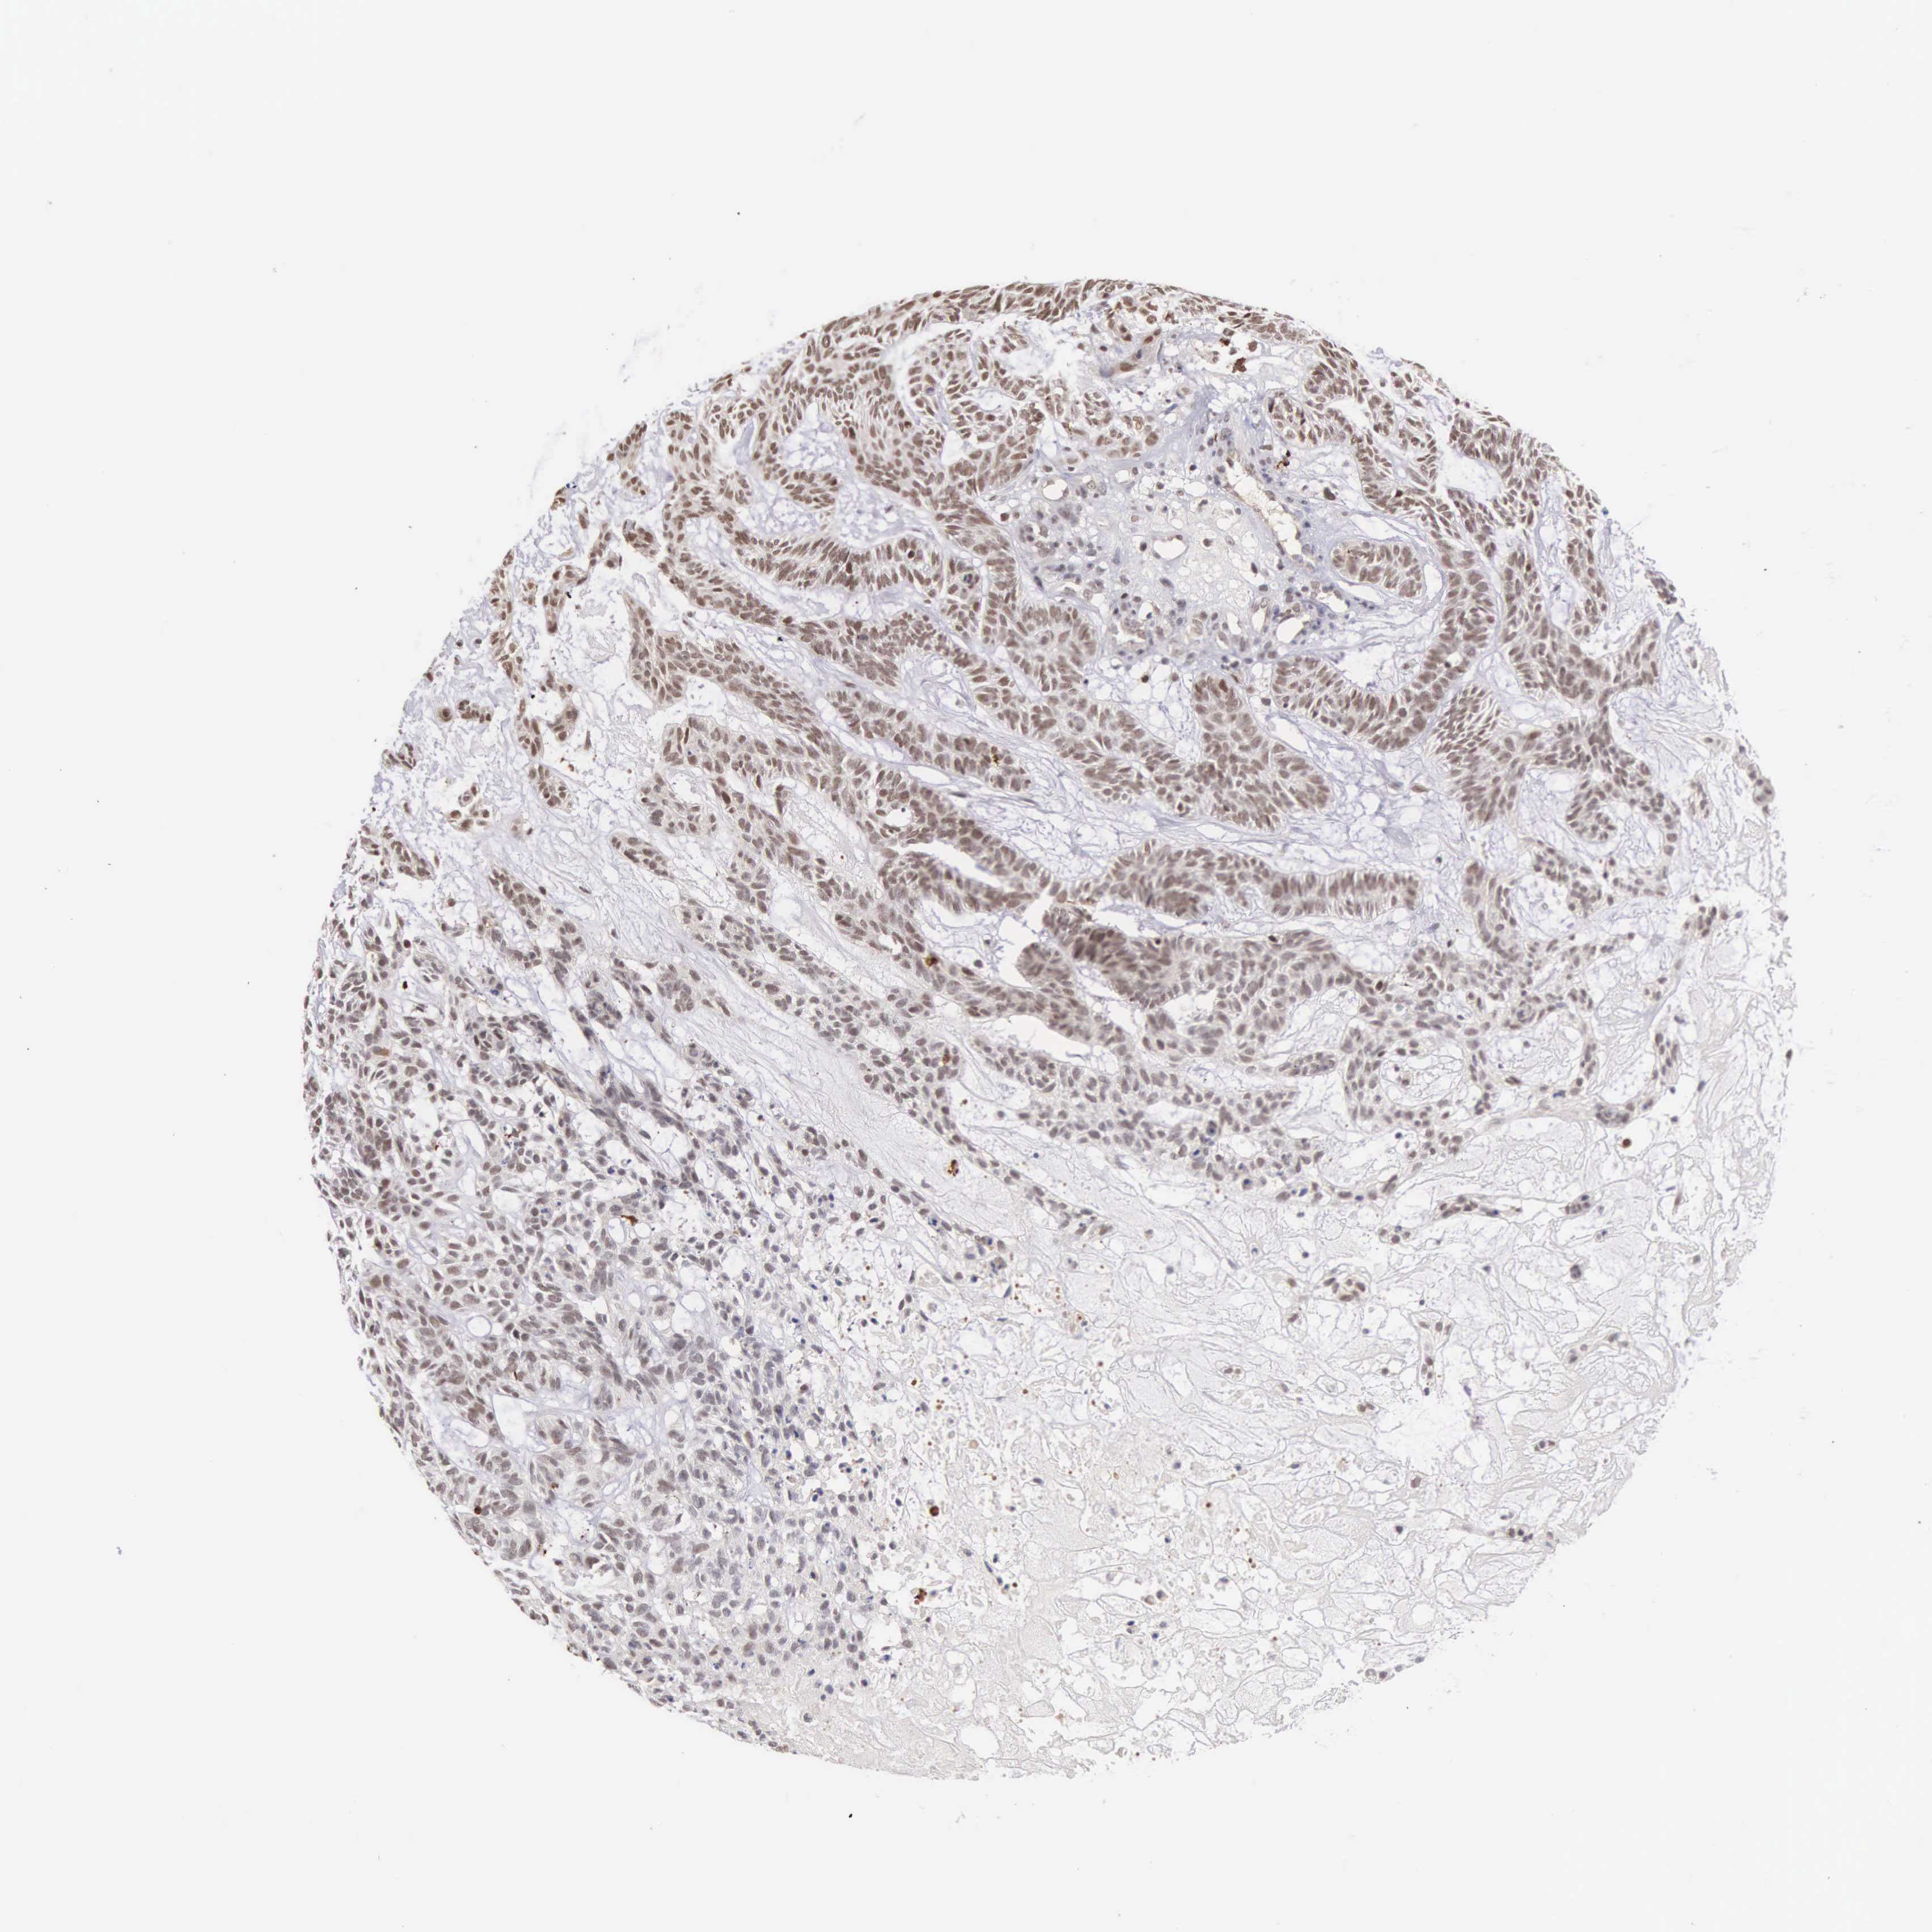

SKIN CANCER - Protein expressioni

A mouse-over function shows sample information and annotation data. Click on an image to view it in a full screen mode. Samples can be filtered based on level of antibody staining by selecting one or several of the following categories: high, medium, low and not detected. The assay and annotation is described here.

Antibody stainingi

Antibody staining in the annotated cell types in the current human tissue is reported as not detected, low, medium, or high, based on conventional immunohistochemistry profiling in selected tissues. This score is based on the combination of the staining intensity and fraction of stained cells.

Each image is clickable and will lead to virtual microscopy that enables deeper exploration of all samples and also displays staining intensity scores, fraction scores and subcellular localization as well as patient and tissue information for each sample.

Antibody HPA000725

Staining

High

Medium

Low

Not detected

Intensity

Strong

Moderate

Weak

Negative

Quantity

>75%

75%-25%

<25%

None

Location

Nuclear

Cytoplasmic/membranous

Cytoplasmic/membranous,nuclear

Squamous cell carcinoma, NOS

Basal cell carcinoma